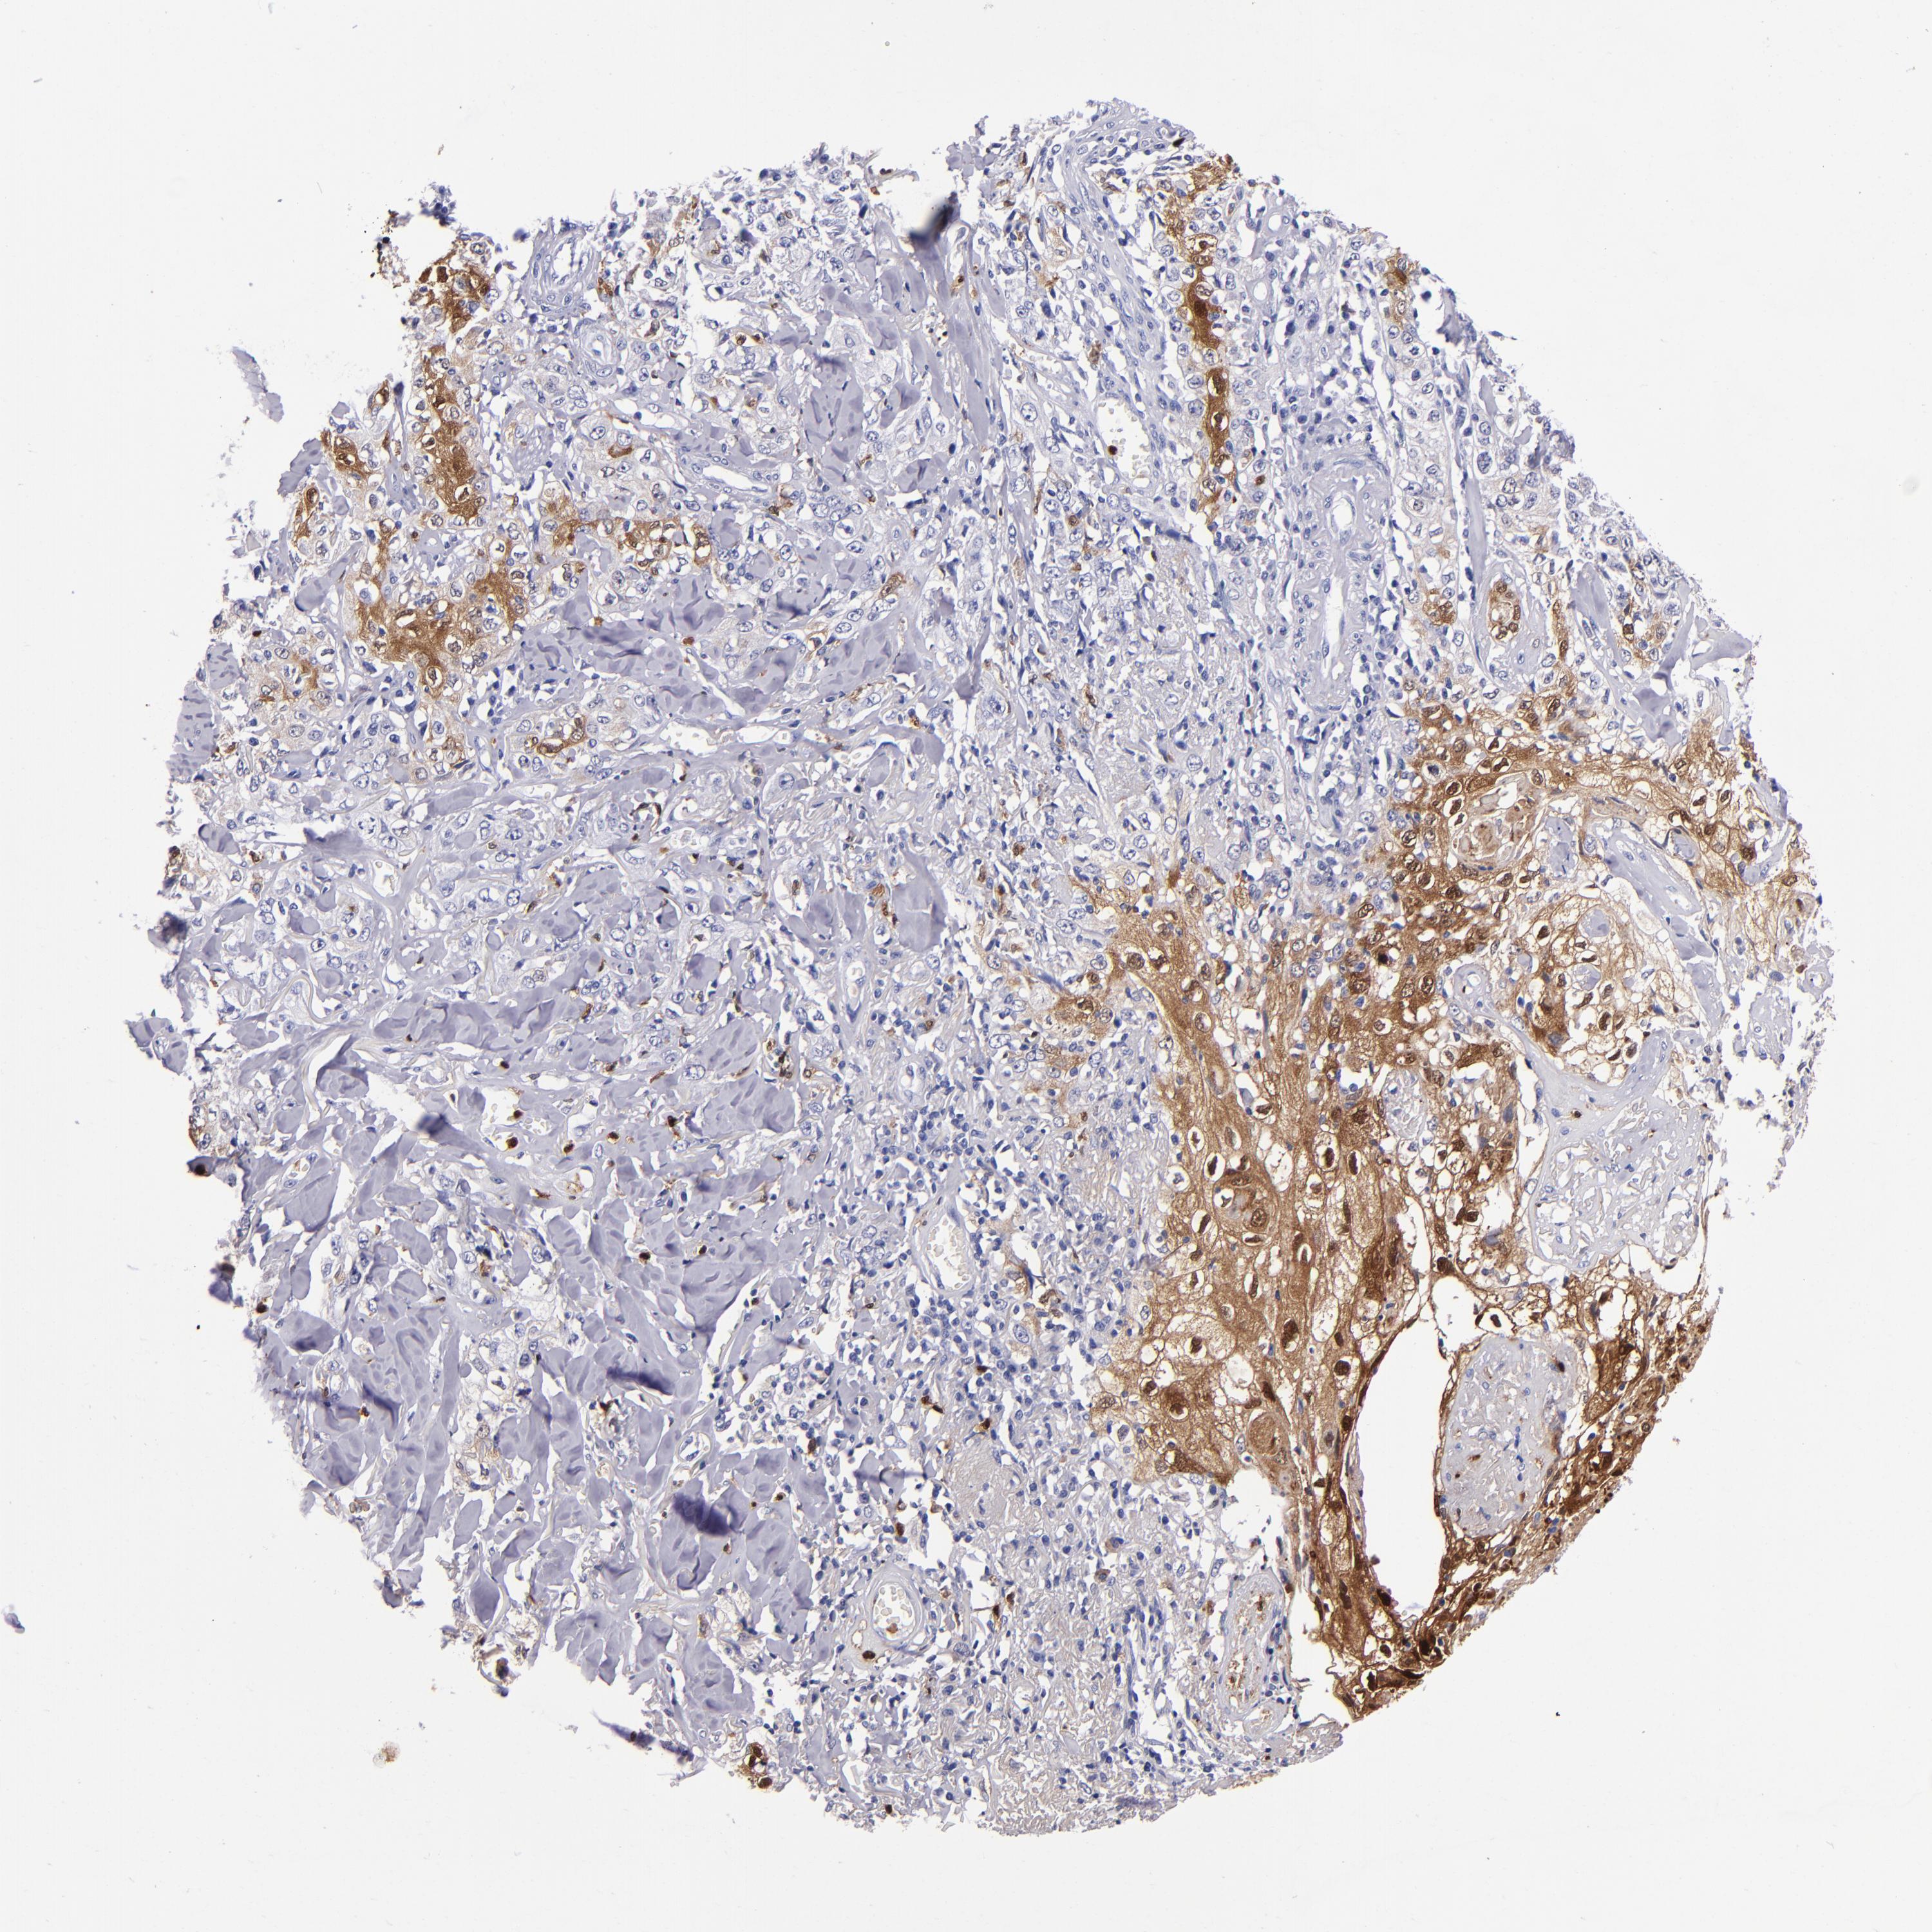

CANCER SKIN CANCER Show tissue menu

Basal cell and squamous cell cancer

Human cancer

SKIN CANCER - Protein expressioni

A mouse-over function shows sample information and annotation data. Click on an image to view it in a full screen mode. Samples can be filtered based on level of antibody staining by selecting one or several of the following categories: high, medium, low and not detected. The assay and annotation is described here.

Each image is clickable and will lead to virtual microscopy that enables deeper exploration of all samples and also displays staining intensity scores, fraction scores and subcellular localization as well as patient and tissue information for each sample.

Antibody HPA024372

Antibody CAB002791

Basal cell carcinoma

Squamous cell carcinoma, NOS

Squamous cell carcinoma, metastatic, NOS